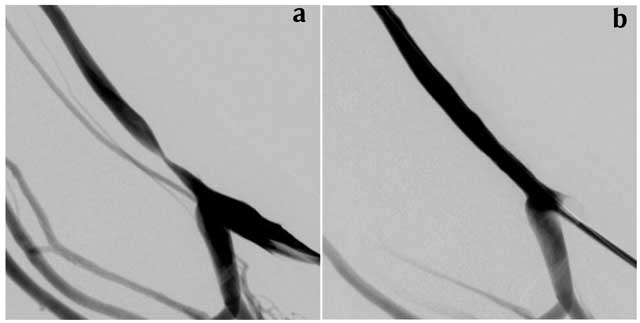

Figures 1a and 1b

left cephalic vein before (a) and after (b) 7 × 40 mm PCB dilation.